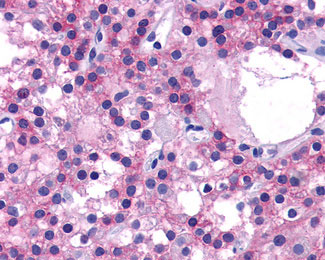

Anti-CASR/Calcium Sensing Receptor antibody IHC of human Parathyroid, Adenoma.

Anti-CASR/Calcium Sensing Receptor antibody IHC of human Thyroid, Medullary Carcinoma.

Anti-CASR antibody APG02427G IHC of human parathyroid. |